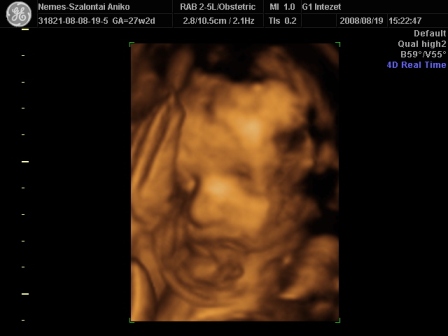

Én Óbudán a G1 intézetben voltam 4D-n. Régen ők voltak a Schöpf-Méreiben. Nagyon-nagyon kedvesek voltak. Nem kaptam letolást, mert késtünk sajnos a dugó miatt. Mondták telefonban, hogy ne idegeskedjek, csak menjünk :D .

Egy nagyon kedves hölgy vizsgált. Mindent megtett, hogy a lehető legjobb képet tudja csinálni a piciről. Nem volt könnyű dolga, mert végig háttal volt, a pofikája előtt volt a köldökzsinór, a két keze és az egyik talpa :lol: . Tornász lesz a gyerek :D . Viszont a fiússágát rögtön megmutatta. Összesen fél órás volt a vizsgálat. A picur méretei teljesen megfelelnek annak, ahány hetes vagyok. Eszerint nov. 9. és 16. között születik. Nem tudom, hogy a saját dokim, honnan szedett 20-át? Mindegy, úgyis akkor jön, amikor jönnie kell. A súlya a picinek 1103 g :) . Jó a szívhang és a köldökzsinór véráramlása is.

Készült DVD az egész vizsgálatról. 4 fényképet kinyomtattak, amit mi választottunk ki. És feltöltötték a honlapjukra az összes képet, amit egy kapott kóddal megnézhet bárki 30 napig. Így a távoli-külföldi rokonok is rögtön láthatják a bébit :).

Szóval teljesen elégedett voltam. Nekem a vizsgálat (hála a babaszobának) ingyenes volt, amúgy 13e Ft.

Kis pofikája I.

Kis pofikája II.